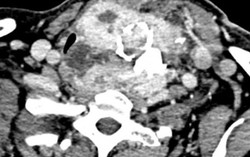

Phòng & chữa bệnh 19:31 16/04/2018Bệnh viện quận Thủ Đức (TP.HCM) vừa phẫu thuật thành công một trường hợp bệnh nhân bị bướu giáp phức tạp.